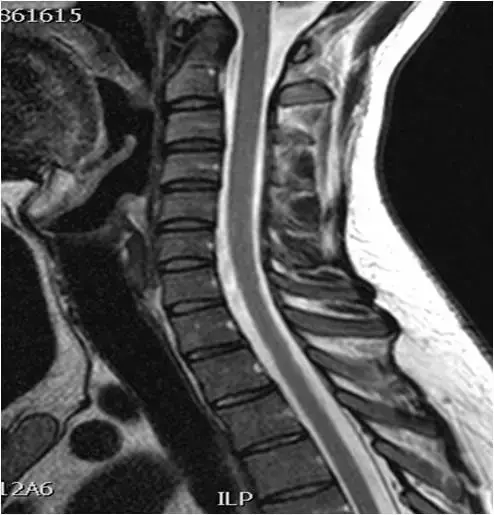

图36:矢状位 T1 TSE图像。 中线部分。生理曲度变直,多个椎间盘向后突出。

图37、矢状位T2 TSE图像。 中线部分。 与图像37相同的患者。颈椎的拉伸。 鉴定出多级椎间盘病变(C3-C4,C4-C5,C5-C6)。